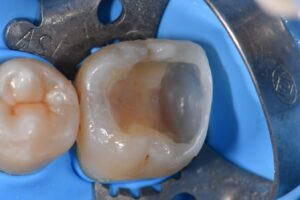

The difficulty and fun with this case was the sheer depth of the free-end extension Class II on the actual clamped tooth. An Omnimatrix was utilized to retain the Garrison Firm Band and driven apically with finger pressure trapping said assembly within the confines of the tines. Hey, that rhymes.

#GarrisonFirmBand #MatrixinMatrix #KerrSimplishade